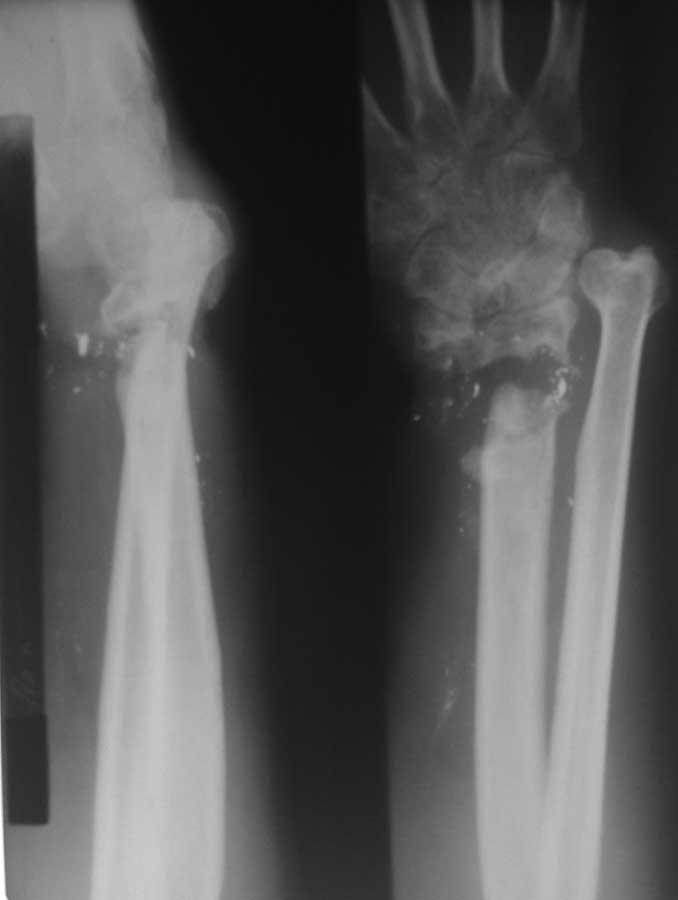

Вот дополнительные снимки

Мы предлагаем: Резекция ложного сустава в области дистального метаэпифиза лучевой кости. Артродез лучезапястного сустава. Пластика дефекта в области луча в типичном месте аутотрансплантантом из локтевой кости на сосудистой ножке. Остеосинтез пластиной. Укорочение локтевой кости. Остеосинтез пластиной.

Изучали ли вы достаточно тщательно ангиограммы пораженного сегмента? Если да, то вы обратили внимание, что в артериальной фазе практически полностью отсутствует контрастирование лучевой артерии в зоне дефекта, тем самым вы имеете разорванную артериальную дугу и стабильный кровоток только в одном бассейне-локтевой артерии, тыльная межкостная не контрастировалась. Невзирая на это, вы предлагаете использовать пластику дефекта трансплантатом локтевой кости на сосудистом пучке (единственном, который объективно сохранился). Не боитесь ли вы возникновения проблем кровоснабжения кисти при выполнении данного вмешательства и как вы готовы бороться с этим (имею в виду оснащение, специалистов по микрохирургии и пр.)-это вопрос номер 2.